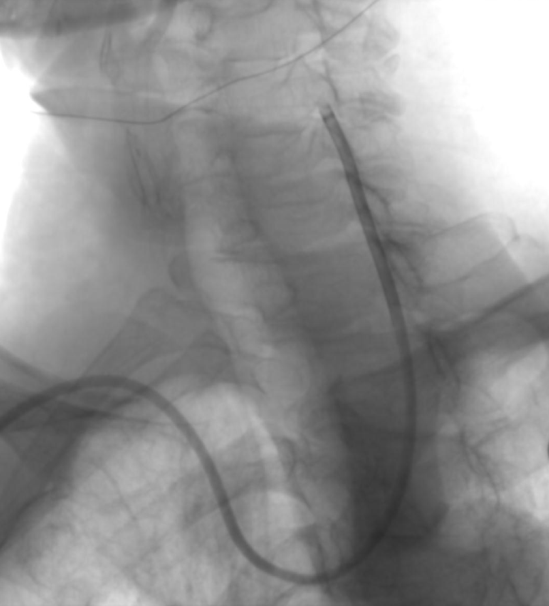

手术过程:

右侧桡动脉穿刺成功后置入6F桡动脉鞘,完成血管造影后更换6F 90cm lonAccess长鞘。泥鳅导丝引导下同轴送入6F 90cm lonAccess长鞘+5F 125cm Simmons II,越过迂曲的右锁骨下动脉,塑形成功并到达左侧颈总动脉。

动脉长鞘怎么置入【康德莱医械】经桡介入LA长鞘+Sim II通路组合处理颈内动脉狭窄_https://www.jmylbn.com_新闻资讯_第17张

动脉长鞘怎么置入【康德莱医械】经桡介入LA长鞘+Sim II通路组合处理颈内动脉狭窄_https://www.jmylbn.com_新闻资讯_第18张

康德莱医械5F 125cm Simmons II+康德莱医械6F 900mm lonAccess长鞘同轴送达左侧颈总动脉末端。